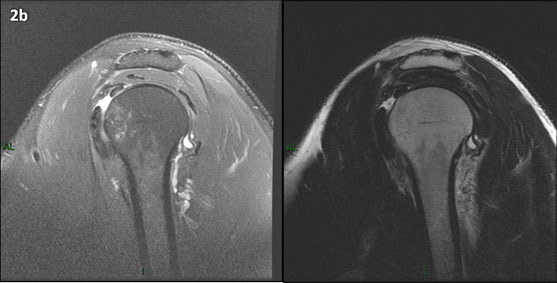

Figura 2 (a-j): Imagens consecutivas de RM no plano sagital nas ponderações T2 com supressão de gordura (DP SG) à esquerda e T2 à direita. Clique na seta para passar as imagens.

Figura 2 (a-j)': Imagens consecutivas de RM no plano sagital nas ponderaçõesT2 com supressão de gordura (DP SG) à esquerda e T2 à direita. Clique na seta para passar as imagens.

Figura 2a’ mostrando os tendões do subescapular (seta rosa), da cabeça longa do bíceps (seta verde), do supraespinhal (seta vermelha), do infraespinhal (seta laranja) e do redondo menor (seta amarela).

Figuras 2b a 2j’: Acompanhando o tendão do redondo menor (seta amarela fina) é possível notar lipossubstituição ao redor da junção miotendínea (setas amarelas grossas) e a atrofia principalmente da porção mais lateral (seta salmão). A porção mais medial (seta branca) tem volume preservado.

Repare que estas alterações também não são evidentes nas imagens com supressão de gordura no plano sagital.